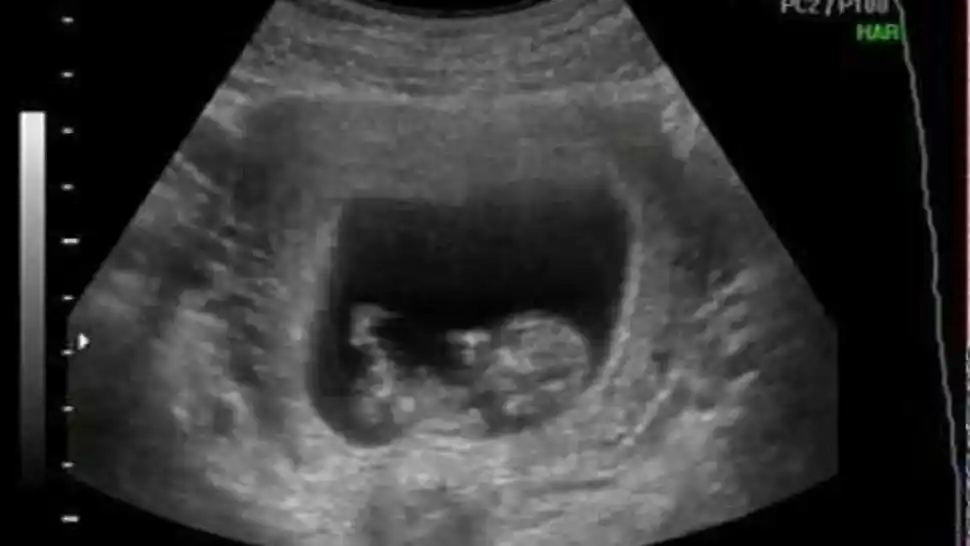

La imagen fue difundida por la madre de la criatura en las redes sociales. La foto se viralizó por el llamativo aspecto del feto.

Sin dudas, uno de los momentos más felices de la vida de algunas mujeres se produce cuando estas se encuentran embarazadas. El proceso en el que las parejas van a realizar estudios y chequeos es mágico, pero tal vez ese no fue el caso de una joven pareja norteamericana que se llevó una inesperada sorpresa. Iyanna Alston, una piba de tan solo 17 años con residencia en Richmond, Virginia, se encontró con un suceso inesperado durante la última revisión de su embarazo. En el ultrasonido, donde le dirían si tendría una niña o un niño, se encontró con una imagen que le llamó mucho la atención. En el momento que la obstetra pasó el escáner a la altura del rostro del feto, este volteó, abrió los ojos y esbozó lo que parecía una sonrisa, sin embargo, lejos de que el resultado fuera una tierna postal, los sensores registraron lo que parecía el retrato de un “bebé demonio”, como la misma Alston lo catalogó. Resulta que la madre adolescente, que en aquel momento estaba en la semana 24 de gestación, va a parir a una nena y a pesar de que la imagen la impactó, ella no deja de sentir amor y ternura por su pequeña. Según los doctores precisaron, la beba se encuentra en perfecto estado de salud y la foto trascendida en redes sociales, no denota ningún signo de malestar en el cuerpo de la criatura. Iyanna publicó los resultados de su visita al consultorio médico en Facebook en en los últimos días de agosto, pero no fue hasta ahora que los hechos comenzaron a compartirse y se hicieron virales; tanto que ahora reúne más de 15 mil reacciones y casi 8 mil comentarios.